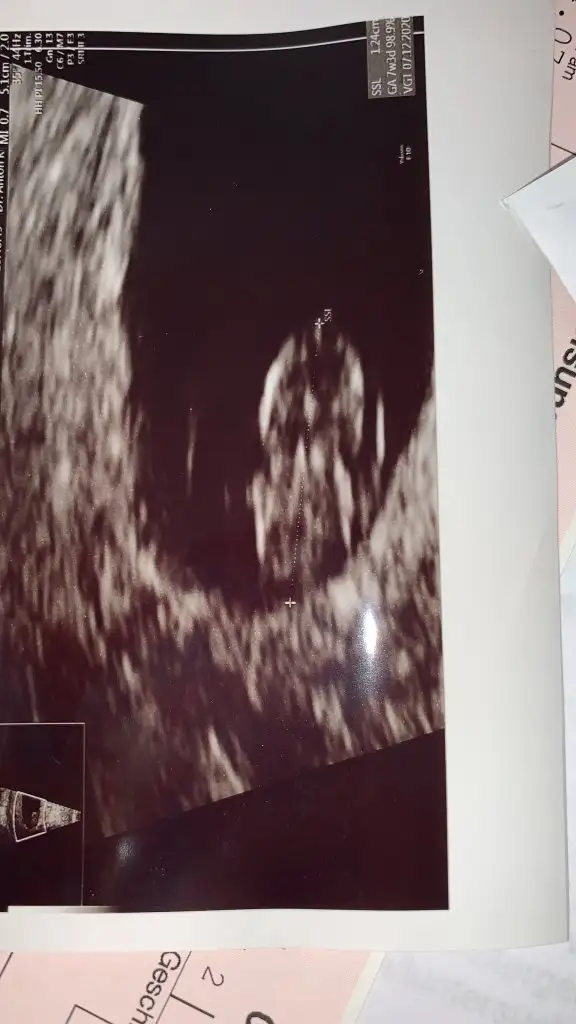

Ben 1 yıllık evliyim 14 nisanda tam bir yıl oldu eşim 6 aylik evliyken sperm sayısında eksiklik ve varikosel ameliyatı oldu sonrasında bize tüp bebek yada aşılama dediler memorialde bizde şubat zaman kaybetmemek icin cok istedigimiz icin tup bebeğe başladık ve acele ettik taze transfer yaptık ve tutmadı negatif büyük hayal kırıklığı oldu sonra dondurulmuş 5.gün embriyosu vardı nisan ayında o olucaktı tutmayınca ilk adet oldum rahim dinlendirme aşamasindaydim negatifi aldık tan sonra 2.adetimi olursam tekrardan transferim olacaktı ama virüsten dolayi erteledik dediler üzüldük ama adetim gelmedi ve hamile olduğumu öğrendim 3 gün gecikmeyle eğer acele etmeseydik belki tüp bebekle hamile kalacaktım o da bizim yavrumuz tabiki ama herseyde bi hayir vardır buna inanıyorum büyük bi mucize bizim için bu. Dondurulmuş embriyomuz için adet olmayı beklerken hamile kaldım ınanamiyorum allaha şükürler olsun.olmaz demeyin olur allah ol der ve olur.